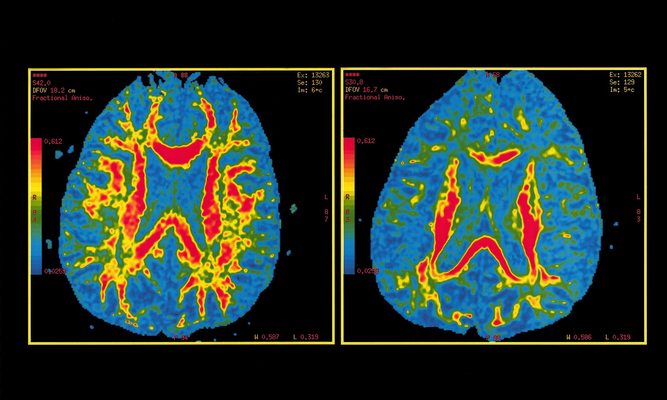

Los autores constataron que el puntaje de PHS era un «fuerte» predictor de la edad de inicio de la enfermedad y la progresión del envejecimiento normal con la enfermedad de Alzheimer, y el deterioro cerebral y cognitivo asociado a ella.